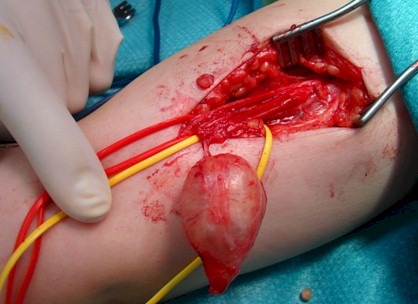

Figura 3: Imagen del schwannoma del nervio mediano disecado

Tras la resección del fascículo afecto se realizó un injerto con nervio sural de unos 5cm de longitud, con sutura termino-terminal de los cabos, con Ethilon® de 8/0 evitando la tensión en la sutura (Figura 4).